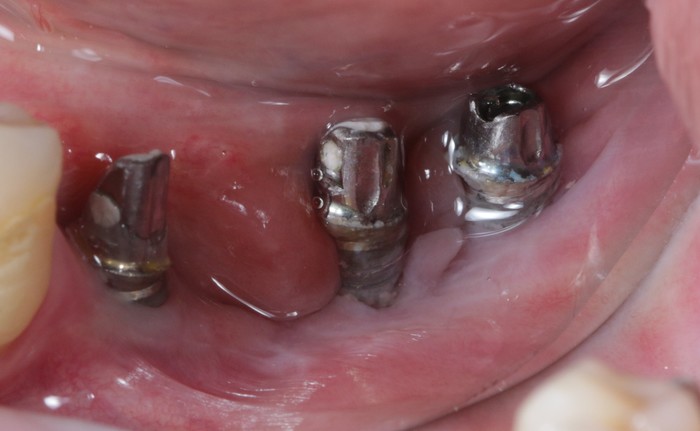

Вот пример того, когда пациент пренебрёг данным правилом:

Мужчине были установлены и спротезированы (временными коронками) имплантаты в другой клинике. После этого он пропал на несколько лет, не закончив полностью свое лечение. Явился лишь тогда, когда почувствовал «дискомфорт».

Кроме несостоятельности старых коронок и пломб, патологической стираемости зубов и т.д. - все эти годы сильно страдала гигиена.

Так выглядят временные (пластмассовые) коронки после их снятия. Они просто утопают в говне налёте. (К слову – поверхность временных коронок отлично собирает на себе налёт, чего в таком количестве не бывает на постоянных, сделанных из керамики.)

Но пациента, видимо, это не особо то беспокоило. Если, даже, выпавшие пару лет назад временные коронки на противоположной стороне его не шибко волновали.